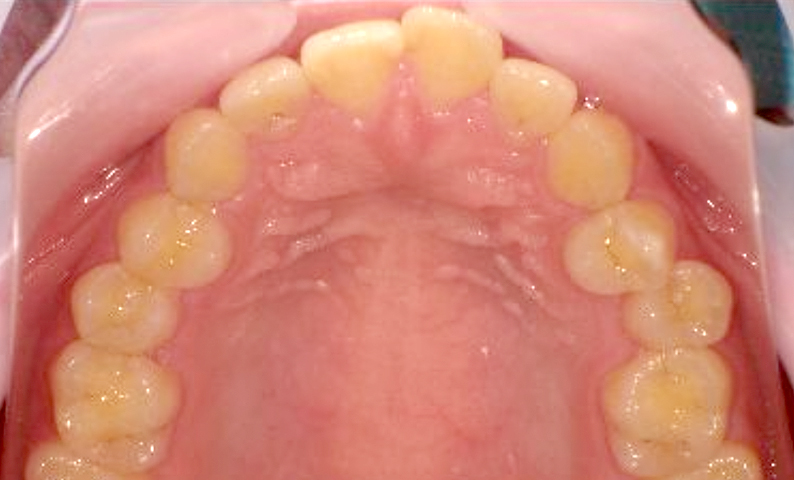

症例_007 前歯「捻転歯」症例

治療期間:10ヶ月金額:30万円+税20代女性少しのねじれ上の前歯だけ

| Before | After |